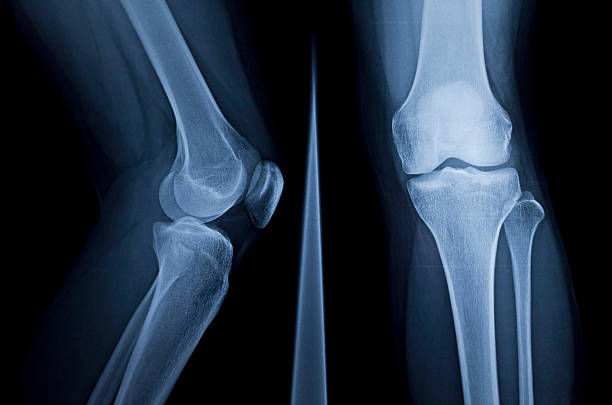

무릎 연골을 정밀 검사하여 찢어진 상태가 좋다는 판단이 선다면 무릎 주변 근력 운동으로 수술을 연기하고 강화하는 것으로 버티는 것이 가능하지만, 파열 전의 상태로 돌아가 반월판 파열된 상태로 살아가야 합니다.

찢어진 연골을 부분적으로 수리하여 원래의 모양으로 회복시키는 치료법도 있는데 얇은 내시경을 삽입하고 미세한 기구로 찢어진 부위를 절제하면서 슬관절의 상태를 관찰하는데 수술 후에는 이틀 정도 재활치료 후 일주일 정도 회복기간을 지나면 일상생활은 가능합니다.

손상이 심해 연골판이 얼마 남지 않아 연골판이 정상적으로 기능하지 못하는 경우 관절염이 생기기 전에 다른 사람의 연골판을 이식할 수 있는데 쉽게 이해하면 각막 이식을 받는다는 행위와 유사하게 타인의 무릎 연골을다. 심장 이식이나 각막 이식 등 사망한 사람에게서 무릎 연골을 채취하여 이식하는 방법입니다. 사람마다 무릎의 크기가 다르기 때문에 자신에게 맞는 크기인지 확인하고, 크기가 비슷하면 연골판 전체를 이식해야 하는데 크게 이식 후 거부반응이 없어 수술로 널리 활용되고 있습니다.

연골을 봉합하는 방법도 있는데 양측 연골판 가장자리의 약 1/3은 혈액으로 재생되어 찢어진 연골을 재생할 수 있지만 내부에 혈관이 없어 부러지면 붙기 어렵기 때문에 혈액이 흐르는 부위의 모양을 찢는 것만으로 봉합할 수 있습니다. 특히 전방십자인대가 동반 손상되는 경우에는 전방십자인대 수술을 하면서 뼈에서 피가 나게 되는데 이 안에 줄기세포가 있어 봉합한 후에 더 잘 붙을 수 있습니다.